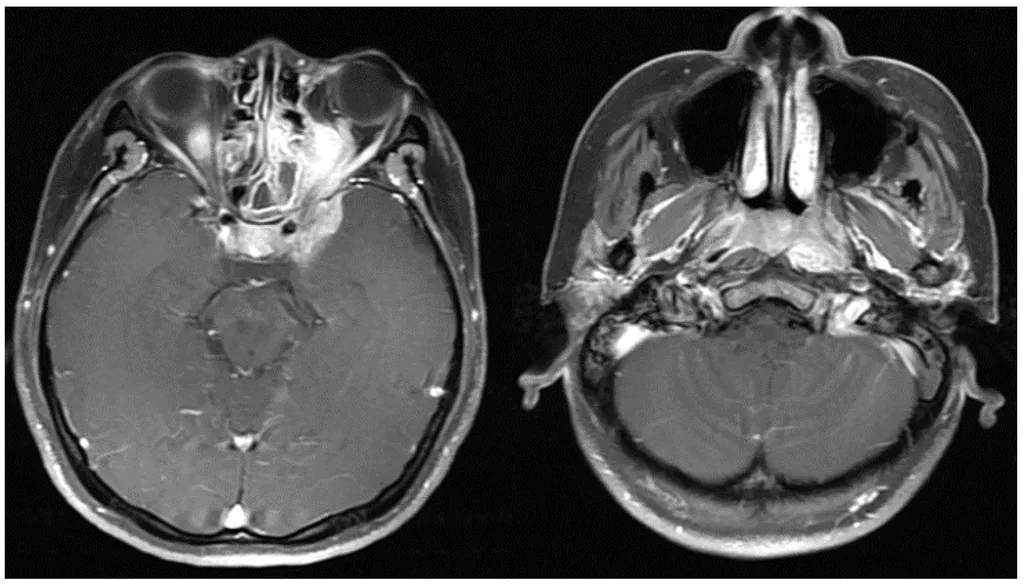

【113-2 醫學(六) 第72題】37歲女性病人,因左上眼瞼下垂與複視而求診,靜脈注射顯影劑磁振造影(如圖),下列何者為最可能之診斷?